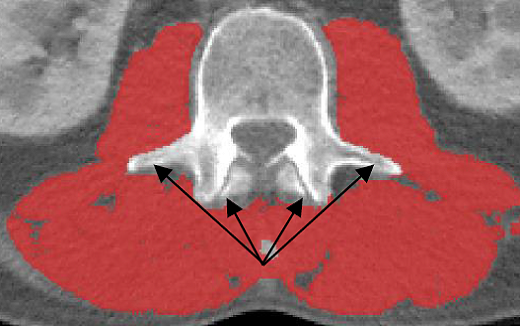

·The area underneath the vertebrae should remain untagged

·If the neural spine is present in the L3, the area underneath the neural spine should remain untagged